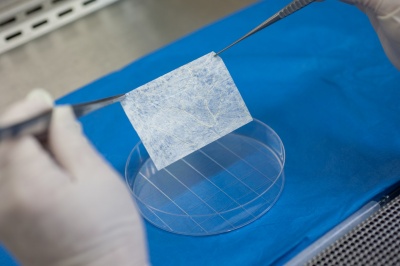

Принцип направленной костной регенерации. Костная регенерация под защитой мембраны Биоматрикс

Принцип направленной костной регенерации. Костная регенерация под защитой мембраны Биоматрикс

Принцип направленной костной регенерации. Костная регенерация под защитой мембраны Биоматрикс